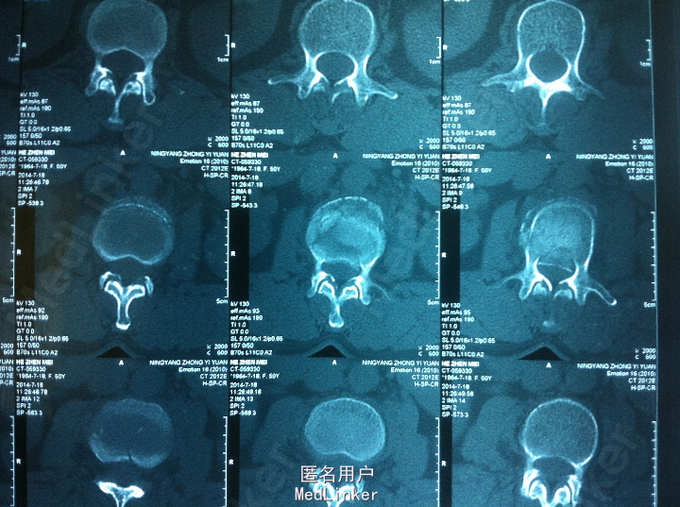

PE:腰部轻度后凸,叩痛,双下肢感觉无减退,双下肢肌力4-5级,巴氏征 阴性。 X-ray:腰2椎体骨折 CT:腰2椎体骨折,椎体后缘不连续 MR:腰2椎体骨折,腰2-3椎体水平硬膜外血肿

诊断:腰椎骨折 腰椎硬膜外血肿 处理:腰椎后路撑开复位内固定

术后1个月,患者轻度腰痛,双下肢感觉无减退,双下肢肌力5级 术后3个月,患者无明显腰痛,双下肢感觉、肌力正常 讨论:1、腰椎骨折累及中柱,无神经损伤表现,是否必须行椎板减压 2、外伤性硬膜外血肿,无神经损伤表现,是否有椎板减压指征